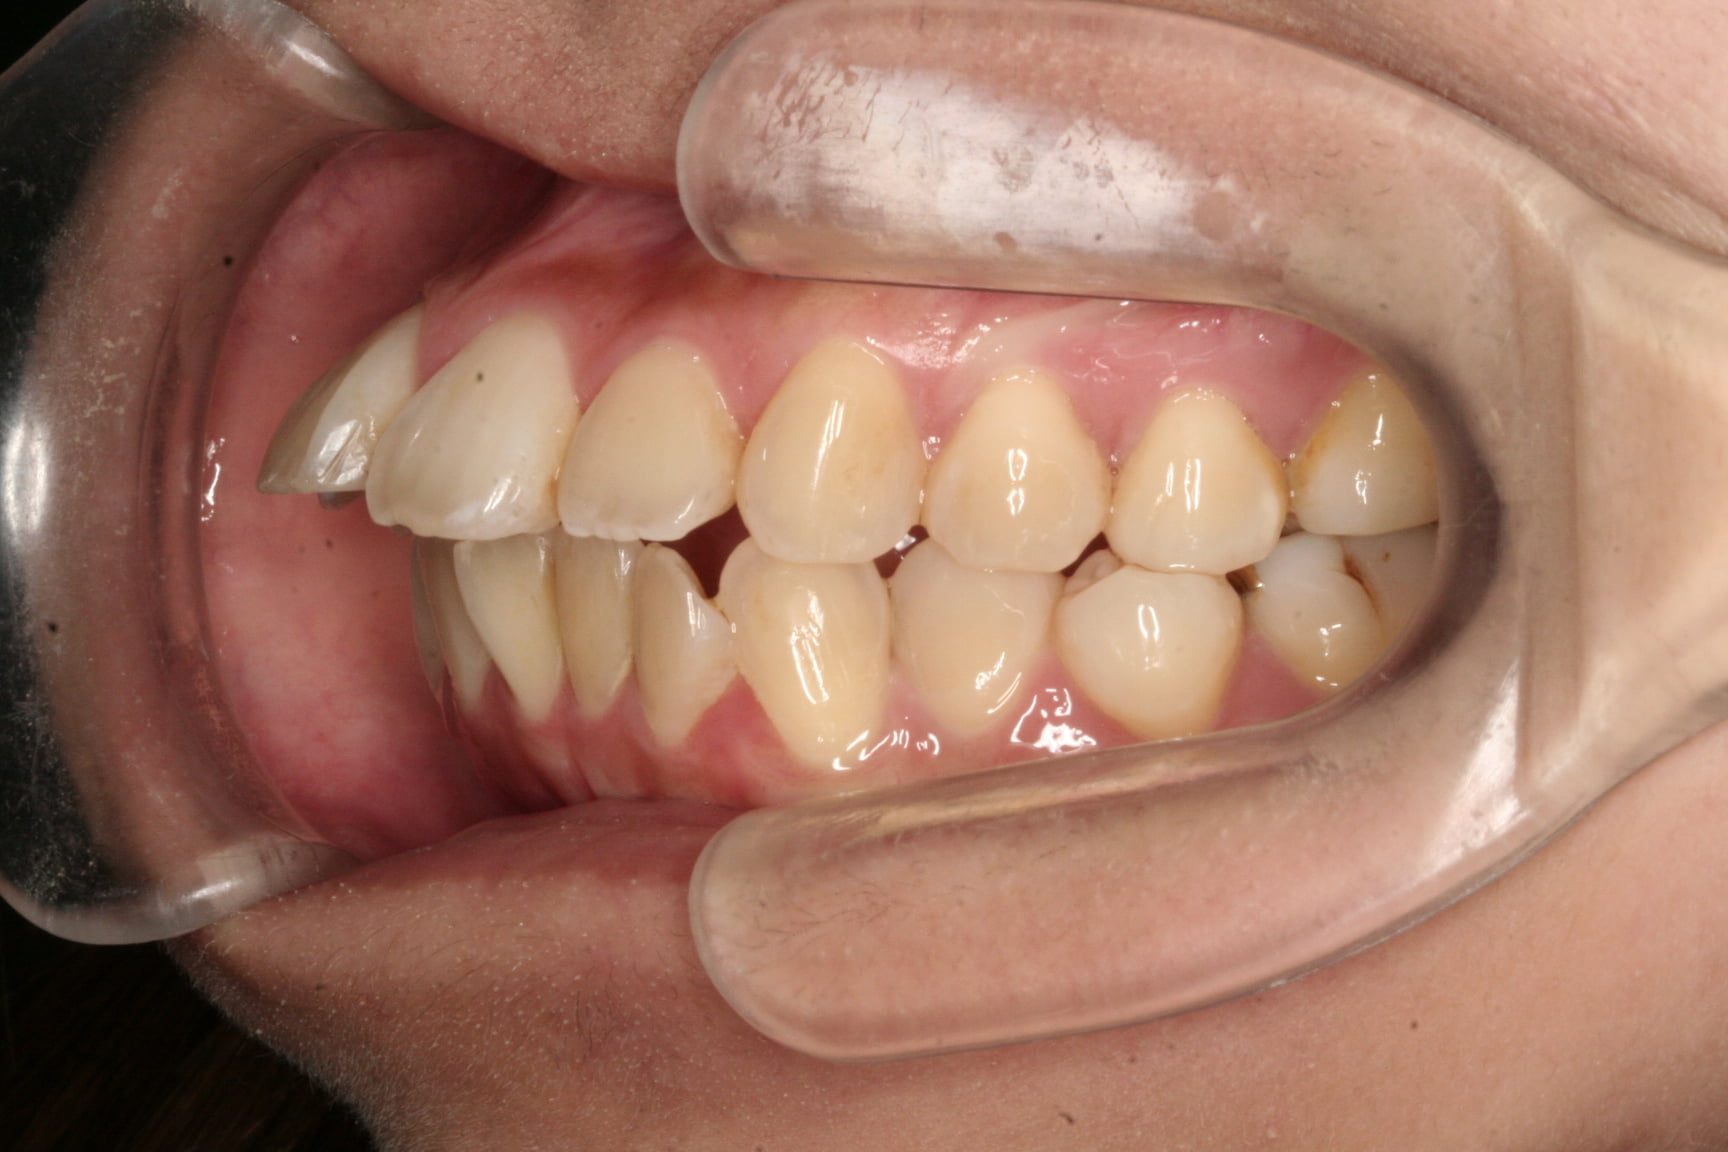

出っ歯を治したい

年齢層 20代

性別 男性

主訴 【主訴】出っ歯を治したい 【診断・症状】上下凸凹、出っ歯(上顎前突)

治療費用 検査・診断:38,500-/裏側矯正治療:1,397,000-(※全て税込)

治療期間 約1年半(20回)

抜歯 有(上4,4のみ)

矯正の装置 裏側矯正(舌側矯正)

副作用、リスク 歯肉退縮,歯根吸収,疼痛,咬合の違和感,装置の違和感,虫歯,歯肉炎

case15_出っ歯_before

Before

case15_出っ歯_after

After